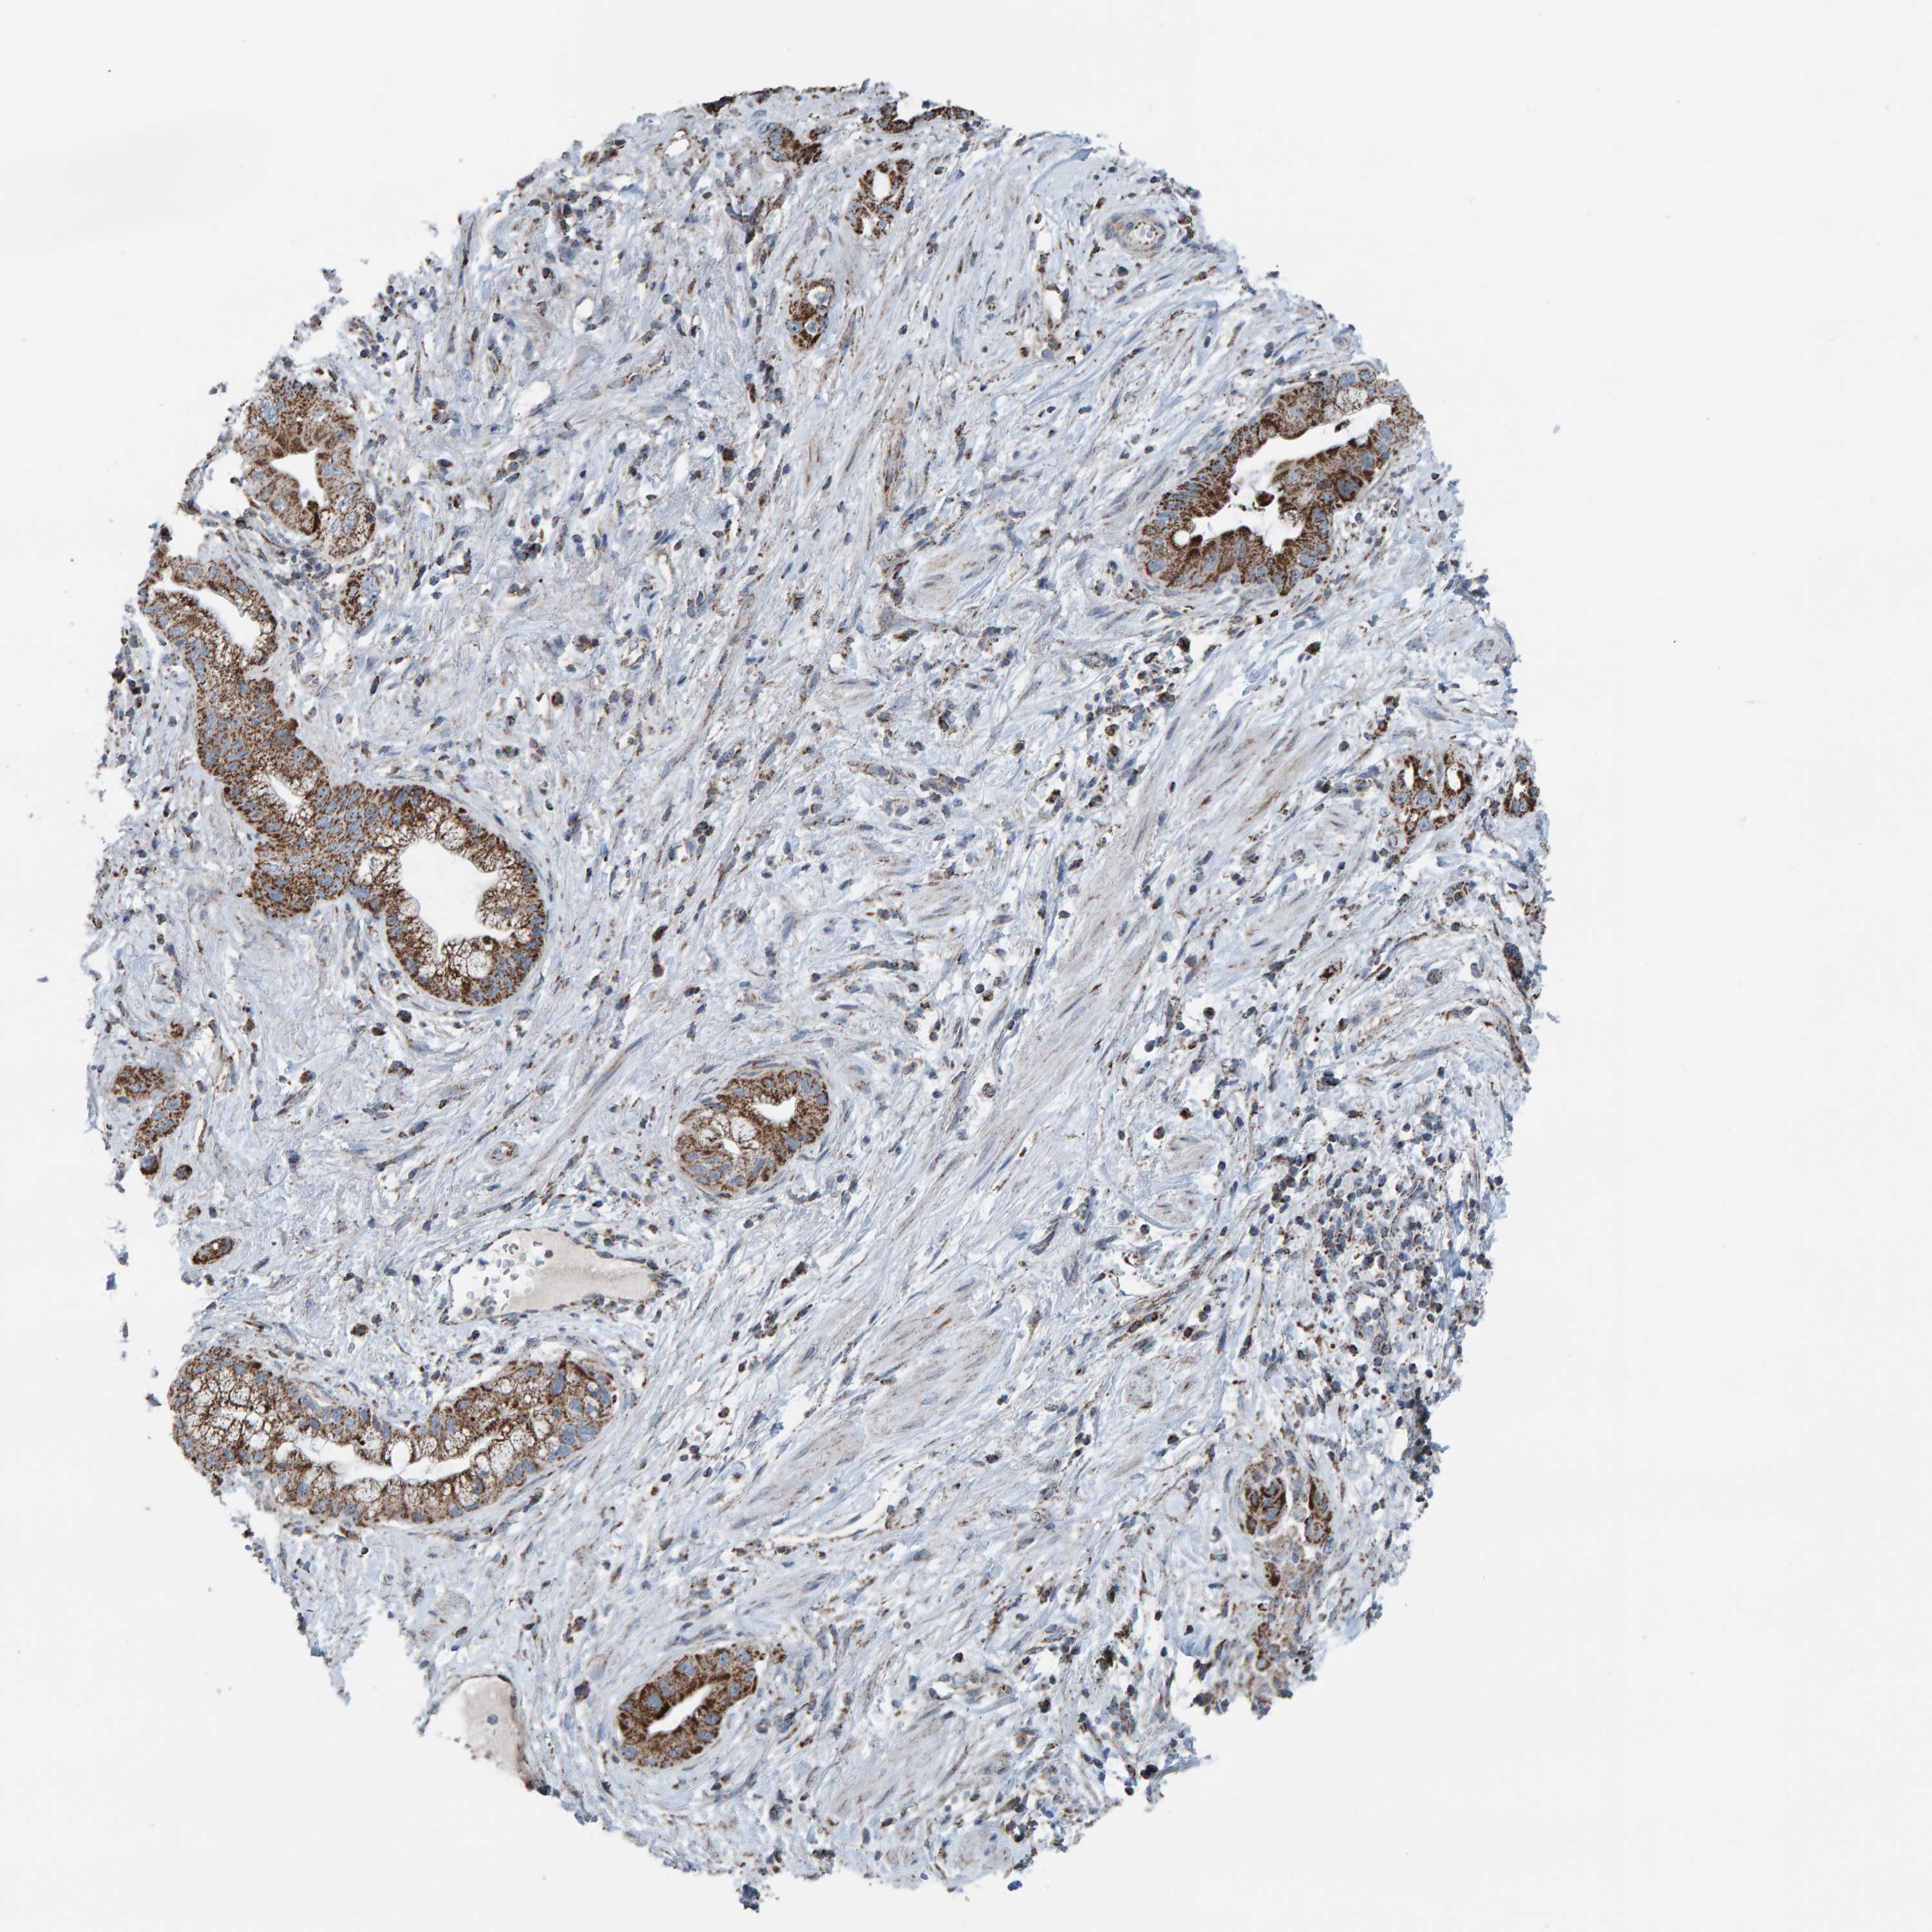

PANCREATIC CANCER - Protein expressioni

A mouse-over function shows sample information and annotation data. Click on an image to view it in a full screen mode. Samples can be filtered based on level of antibody staining by selecting one or several of the following categories: high, medium, low and not detected. The assay and annotation is described here.

Note that samples used for immunohistochemistry by the Human Protein Atlas do not correspond to samples in the TCGA dataset.

Antibody stainingi

Antibody staining in the annotated cell types in the current human tissue is reported as not detected, low, medium, or high, based on conventional immunohistochemistry profiling in selected tissues. This score is based on the combination of the staining intensity and fraction of stained cells.

Each image is clickable and will lead to virtual microscopy that enables deeper exploration of all samples and also displays staining intensity scores, fraction scores and subcellular localization as well as patient and tissue information for each sample.

Antibody HPA023806

Staining

High

Medium

Low

Not detected

Intensity

Strong

Moderate

Weak

Negative

Quantity

>75%

75%-25%

<25%

None

Location

Nuclear

Cytoplasmic/membranous

Cytoplasmic/membranous,nuclear

Adenocarcinoma, NOS